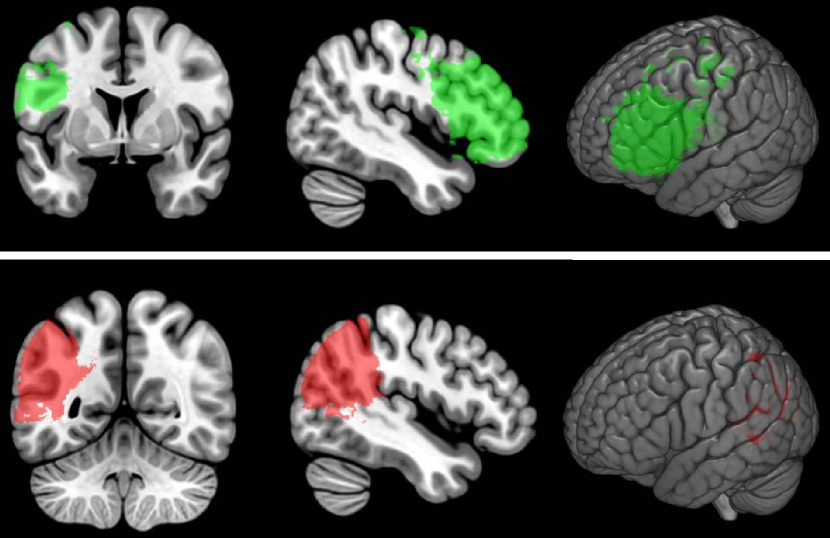

Figure 4 shows the results of permutation-based cluster size correction (at ) for simulated deficit scores of percent damage in BA 45 (top row) and BA 39 (bottom row). It is immediately apparent that the identified region expends beyond the bounds of the true region, covering an area that is perhaps twice the size of the Brodmann Area where percent damage was used as the behavioral score.

For comparison, we used the maximal t-value from the same 1000 permutations to compute permutation-based FWER-corrected thresholds for each of these analyses. The resulting t-thresholds were 5.52 for BA 45 and 5.39 for BA 39 and the thresholded maps are shown in Figure 5. This approach did a reasonably good job of identifying the critical regions.